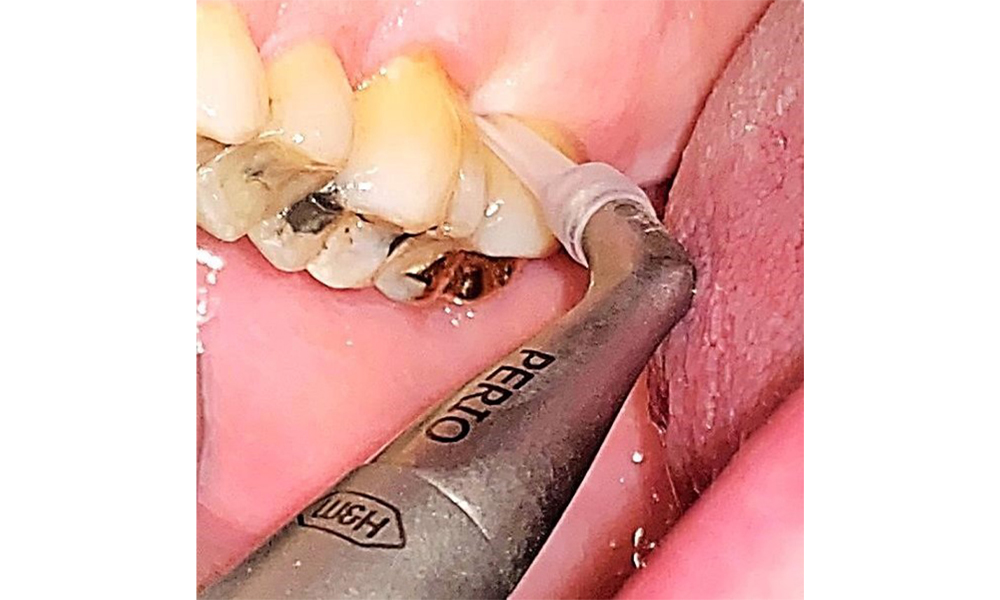

The patient has a full dentition with 28 teeth, which includes amalgam and composite fillings in the molar and premolar regions. There is a visible clinical marginal gap present on tooth 14. Tooth 27 has an adequate gold inlay. There are also generalized attritions and abrasions. (Fig. 2, Fig. 3, Fig. 4, Fig. 5, Fig. 6)

The patient has stage II, grade B periodontitis (5). At 1 to 3 mm, the clinical probing depths were within the physiological range. Localized probing depths of 5 mm were observed on the mesiopalatal aspects on both 17 and 27. There are generalized recessions of 1–3 mm with partial loss of the interdental papillae (Fig. 2, Fig. 3, Fig. 4)